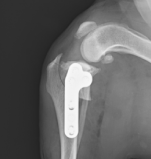

橈尺骨の骨折

上腕骨の骨折

治療には多くの整形疾患で手術が必要になります。術式は折れ方や場所、脱臼の場所などにより様々で、多様な方法を組み合わせて行います。

手術器具は、整形用ドリル(骨を切ったり、スクリュー(ネジ)用の穴を開けたりします)、整形用ラウンドバー(骨を削る器具です)、各種骨プレート・スクリュー、ワイヤー、ロッキングプレート・ロッキングスクリュー(通常のプレートより強固な固定が可能です)、骨セメント、整形器具を揃えており、幅広い手術に対応可能です。

橈尺骨骨折

プレートスクリュー固定

上腕骨骨折

ピン・スクリューによる固定